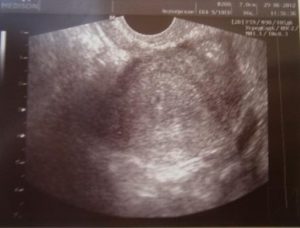

УЗИ на ранних сроках беременности позволяет определить местоположение зародыша. Если он находится в матке, будущая мама может быть спокойна. Однако иногда УЗИ не фиксирует плодное яйцо, несмотря на высокий уровень ХГЧ и положительный тест. Почему так происходит? Может ли УЗИ ошибаться?

Такой результат вызывает беспокойство у специалистов. Отсутствие плодного яйца может указывать на внематочную беременность. Эмбрион обычно становится видимым с пятой акушерской недели, поэтому врачи не рекомендуют проводить ранние обследования, чтобы избежать неверного диагноза.

Женщины часто стремятся узнать о беременности на самых ранних сроках, особенно если она нежелательна. Прерывание беременности медикаментами возможно только на начальном этапе. Если врач не обнаружил плодное яйцо в матке при положительном тесте, женщину не смогут направить на аборт или зарегистрировать.

Если УЗИ не подтвердило беременность (при положительном тесте), специалист рекомендует повторное обследование через две недели. Возможно, эмбрион слишком мал для визуализации.

Отсутствие видимости эмбриона на УЗИ в ранние сроки может быть связано с несколькими факторами:

- Слишком ранний срок. На начальных этапах сложно отличить плодное яйцо от полипов матки;

- Отечность слизистой матки из-за воспалительных процессов;

- Использование устаревшего оборудования;

- Нестандартная форма матки;

- Недостаток опыта у врача-узиста, что может привести к ошибкам в диагнозе.